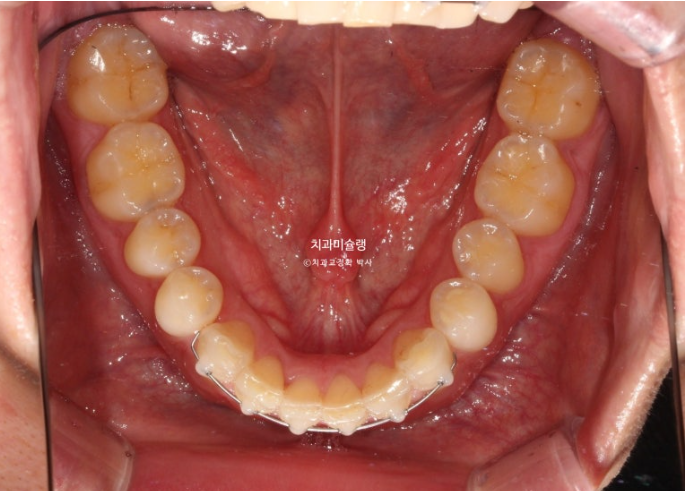

25.08

치료시작 4개월차 모습입니다.

윗니배열은 완벽하며

아랫니 배열이 조금 부족합니다.

약 2개월간 교정을 더 진행하여 10월, 드디어 장치를 뗍니다.